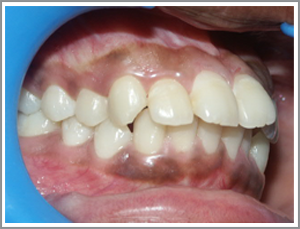

Case 2

Before

After

JKL a 15 year old boy had severe crowding of teeth (Angles class I malocclusion with crowding)

Problem list : unsightly appearance of teeth and recession of the gums due to outward projection of the canines.

Treatment plan : Extraction case - The case was treated with extraction of four first premolars and the alignment of the canines into the extraction spaces. The canines are very rarely extracted. They are usually aligned by extracting premolars since they are crucial for normal functions like biting and also very important for the pleasing appearance of the teeth.

Treatment time : 15 months